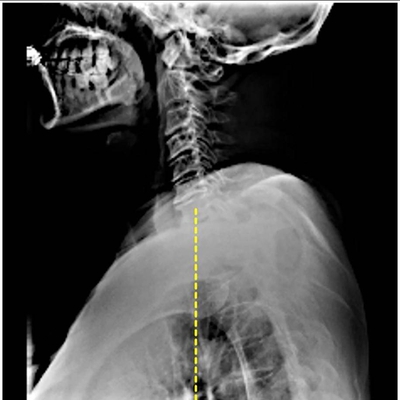

Click on an image below to view more info.